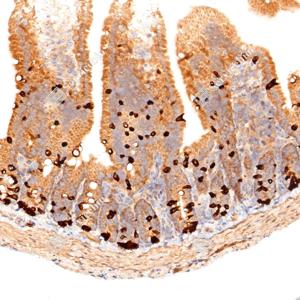

| IHC检测Smad2蛋白(货号 GB15511). 样品: 小鼠小肠, 4%多聚甲醛 (货号G1101) 固定12-24小时. 抗原修复: 抗原修复仪(货号 ARI-4),Tris-EDTA抗原修复液(pH 9.0) (货号G1203), 水浴100℃, 25分钟. —抗: 1: 400稀释, 4℃ 孵育过夜. 二抗: S-vision免疫组化多聚二抗(山羊抗兔),即用型 (货号G1302), 室温孵育20分钟. |